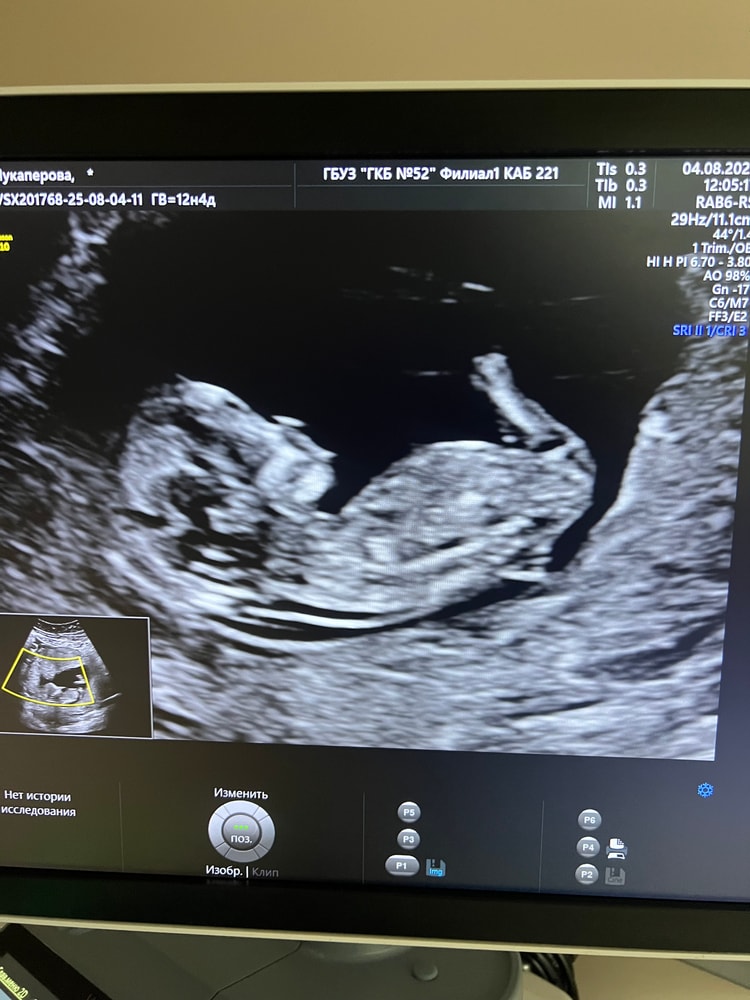

Анализы, скринингия, как и многие, хочу погадать и тут 😁 как думаете, кто?) другого фото нет 🤷🏽♀️

А я вообще не вижу, мне кажется, даже полового бугорка нет. То, что принимают за половой бугорок, как будто часть чего-то, но не он

Скорее за девочку)

Вероятно это половой бугорок и он скорее вниз.

Но, у моего младшего бугорок тоже был вниз, правда он иначе выглядел.

Потому, я за девочку )

Я тоже думаю что это половой бугорок девочки, фото просто не оч удачное, нога тут как бы на заднем фоне туда куда нужно смотреть)

Анастасия Нефедова, где вы писюн увидели? Половой бугорок параллелен позвоночнику, а не находится под углом